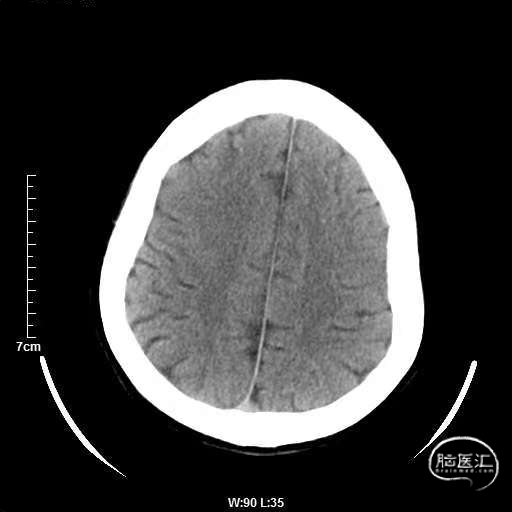

颅脑CT:未见明显缺血/出血病灶。

CTA提示:右侧椎动脉纤细,左侧椎动脉V1、V4段纤细。

术后CT:未见明显脑出血,双侧小脑低密度影。

术后CTA:Bridge药物支架形态良好,前向血流良好。

术后半年CTA:Bridge支架形态及贴壁良好,前向血流正常。